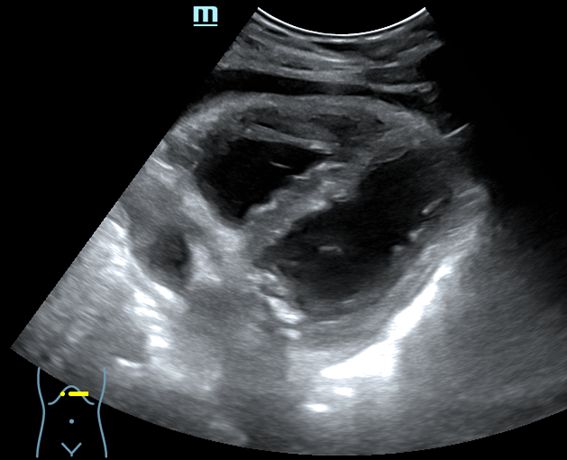

- Ecografía abdominal: ventana subxifoidea: buena contractilidad miocárdica, cámaras de tamaño normal, derrame pericárdico. Corte epigastrio: cava de tamaño y colapsabilidad normal.

Diagnóstico diferencial: la ecografía pulmonar descarta: neumotórax, derrame pleural y consolidación pulmonar. La ecografía abdominal descarta: tromboembolismo pulmonar, insuficiencia cardíaca y taponamiento cardíaco.

• Ecografía transtorácica: buena función ventricular. No valvulopatías. Derrame pericárdico de 1,3 cm.